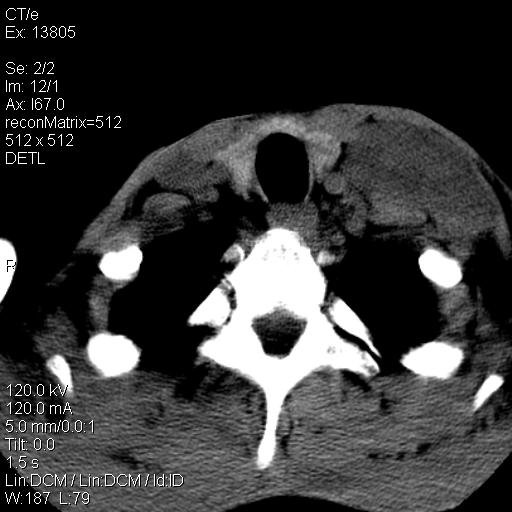

上腹部疼痛一月,呕吐10天,发现左侧颈部包快10天 胸部cr片未见明显异常。

左侧胸锁乳突肌下方、颈血管旁低密度肿块影,肿块密度尚均匀,边缘大部分清楚,邻近组织稍受压移位。考虑颈部神经鞘瘤可能性大。